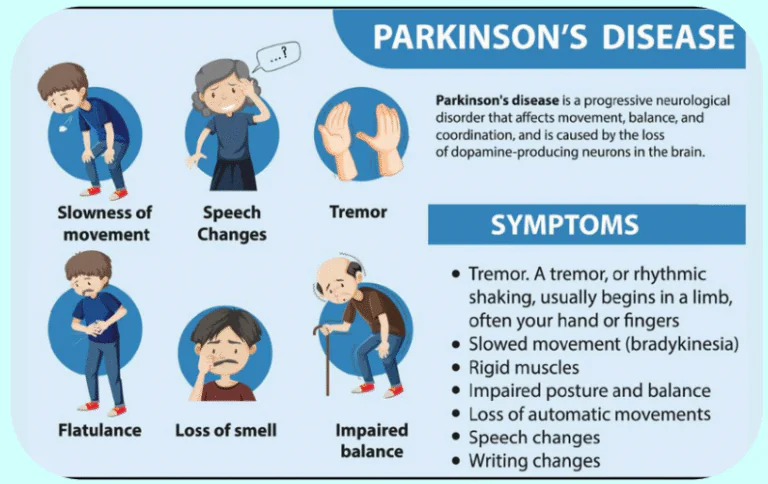

PARKINSON’S DISEASE

Definition

Parkinson’s disease is a progressive neurological disorder that affects movement. It occurs due to reduced dopamine production in the brain.

Common Symptoms

- Tremors

- Muscle stiffness

- Slowed movements

- Balance problems

- Speech changes

How Stem Cell Therapy May Help

Stem cell therapy may support dopamine-producing neurons and reduce inflammation in the brain. It may help improve motor function and coordination when combined with medications and physiotherapy.

Diagnostic Tests

- Neurological examination

- MRI brain

- Movement assessment scales

- Blood screening

Procedure

- Neurological assessment

- Imaging review

- Medical clearance

- Controlled stem cell therapy

- Physiotherapy and motor training

- Ongoing monitoring